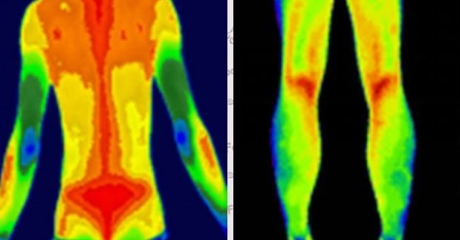

血管病變預(yù)警

自動(dòng)標(biāo)注肢體溫差>1℃的區(qū)域(提示血栓風(fēng)險(xiǎn))

動(dòng)態(tài)監(jiān)測(cè)糖尿病足微循環(huán)變化

案例:北京某三甲醫(yī)院用其提前7天預(yù)警糖尿病患者足部壞死風(fēng)險(xiǎn)

炎癥可視化

智能識(shí)別類風(fēng)濕關(guān)節(jié)炎的“梭形熱區(qū)”

量化評(píng)估強(qiáng)直性脊柱炎進(jìn)展程度

(插入示意圖:脊柱炎癥熱圖 – 紅色熱區(qū)與MRI病灶位置完全吻合)